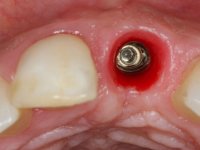

3) Colocação de um implante no espaço criado na zona do 21 associada a uma regeneração óssea guiada da zona,

A comparação entre o óxido de zircónio e o dissilicato de lítio mostra que o último pode sofrer ataque ácido e ser silanizado e assim ser preparado para uma cimentação adesiva. Uma dica: no sentido de criar no coto de óxido de zircónio uma superfície susceptível de ser gravada pelo ácido, a superfície a ser colada pode ser recoberta com uma fina camada de cerâmica de adesão antes de modelar a coroa. Para este propósito, a ceram Zirliner é aplicada primeiro, depois aplica-se uma camada de ceram de dentina profunda na tonalidade desejada. Como resultado, a cor da dentina ilumina a restauração a partir do seu interior e cria a possibilidade de ser aplicado um protocolo de cimentação adesiva.

A confecção de um coto de óxido de zircónio com uma coroa de cerâmica vítrea prensada de dissilicato de lítio mimetizou perfeitamente os dentes vizinhos.